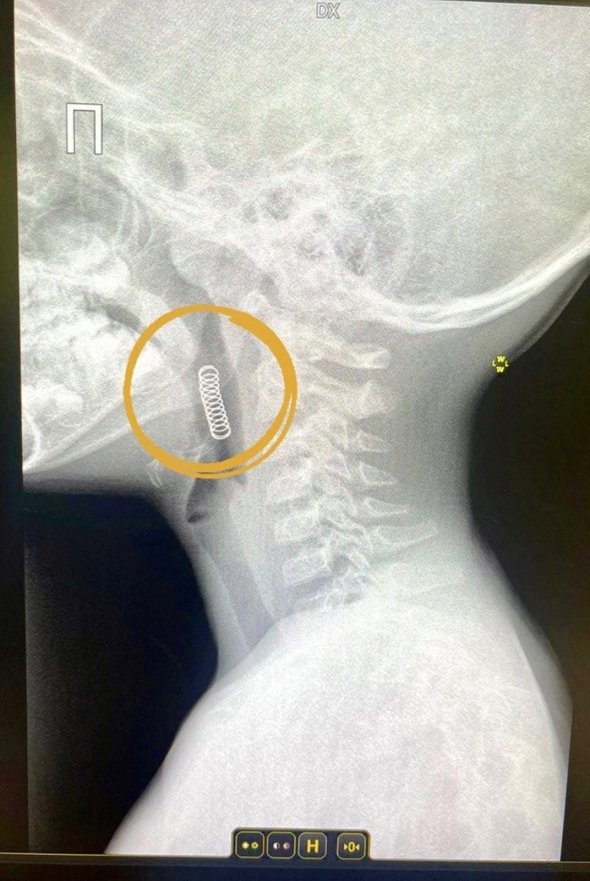

Мальчика с жалобами на дискомфорт в горле доставили в областную больницу № 4 в Ишиме. Родители рассказали, что сын случайно проглотил пружинку, отскочившую во время игры. Медики установили, что инородный предмет попал в глотку и застрял между надгортанником и небной миндалиной.

фото: vk.com/oblzdrav72